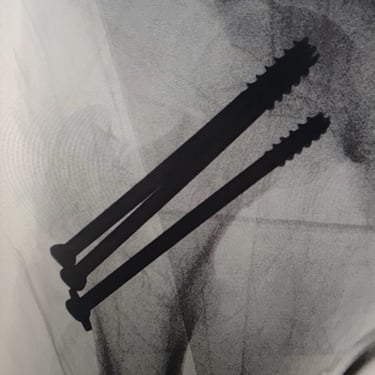

Gallery